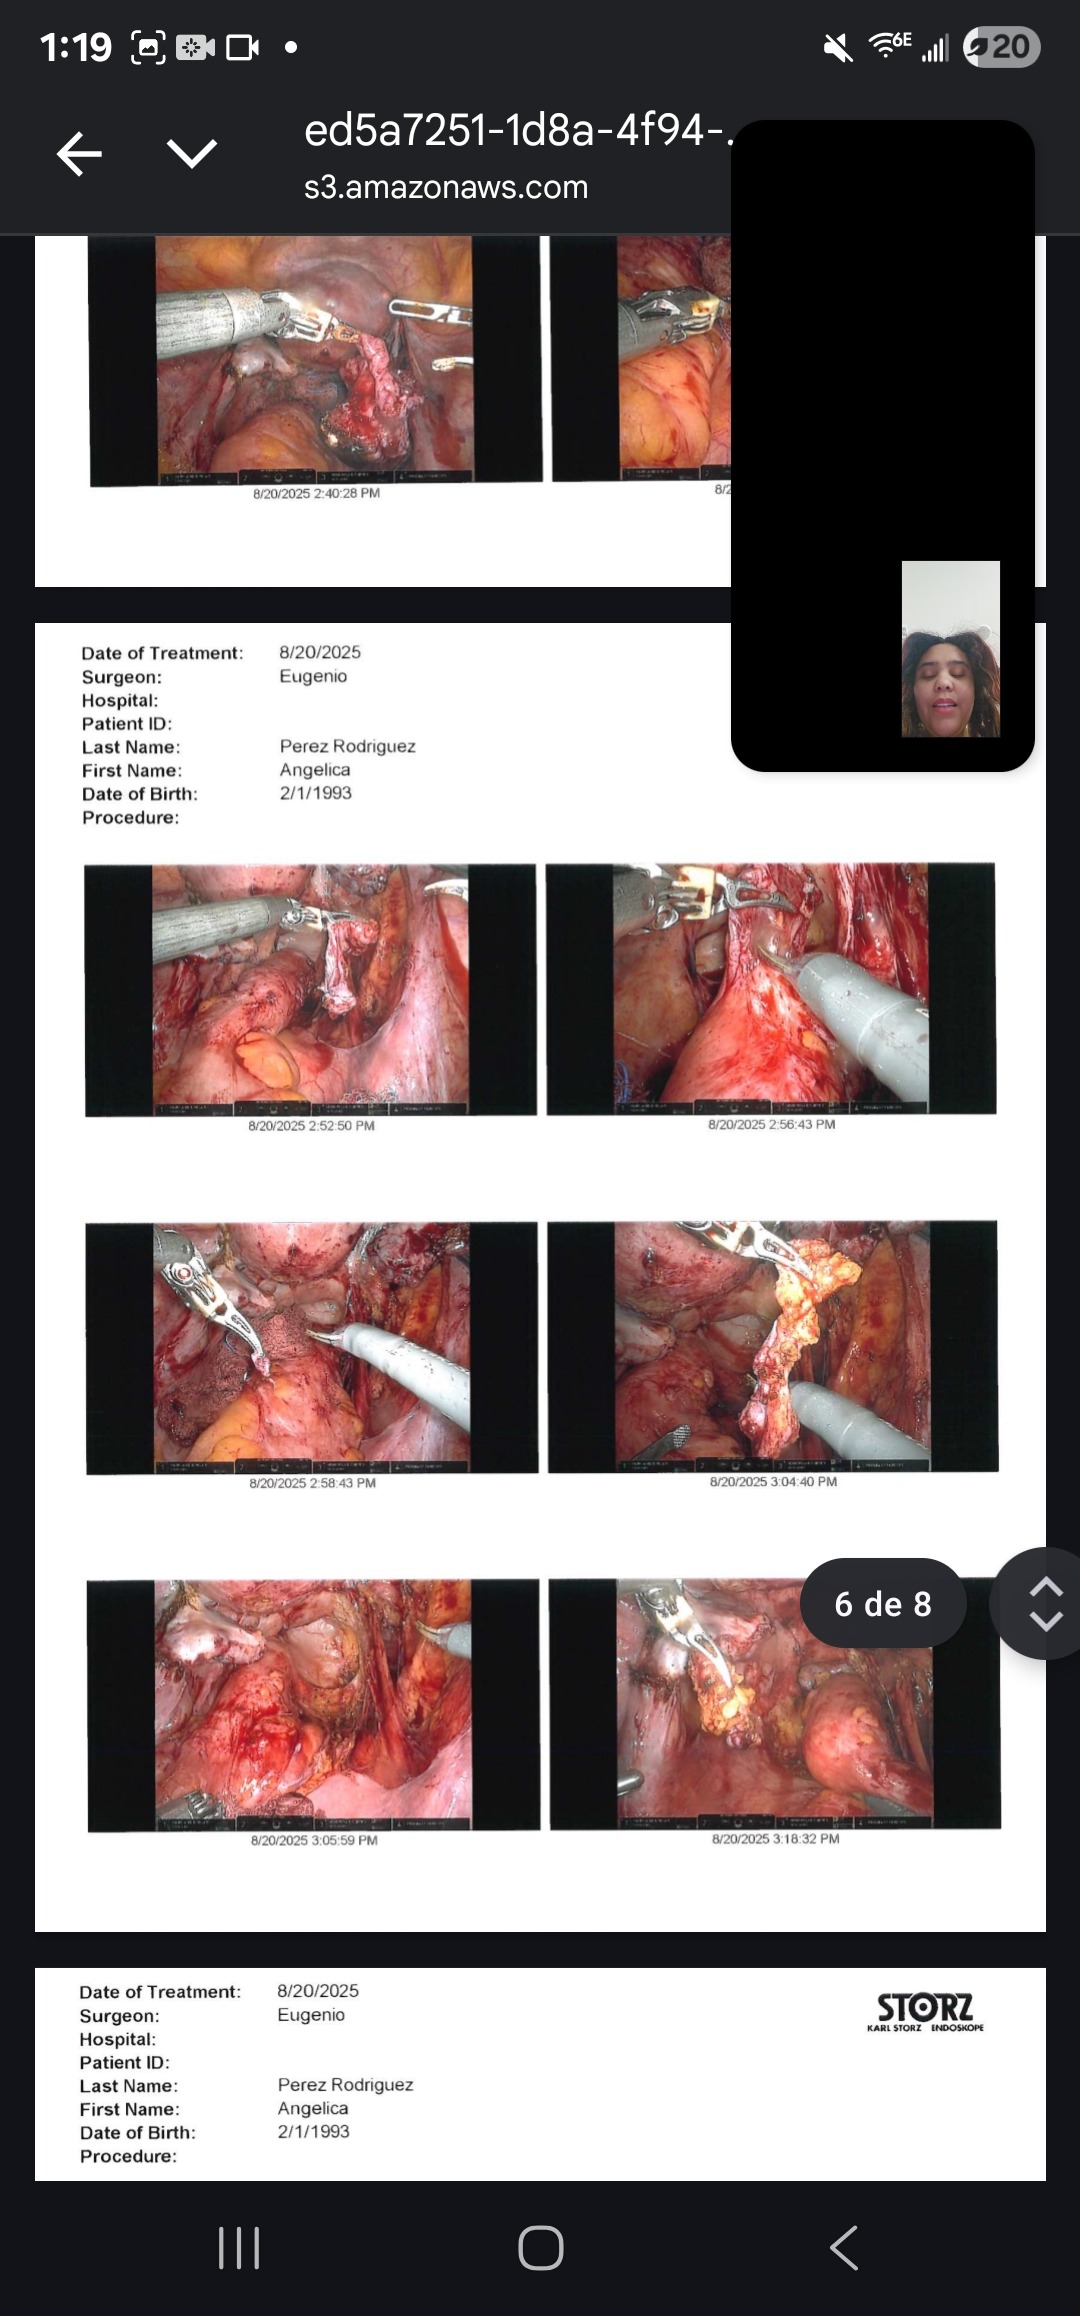

My name is Angelica, and I am fighting Stage 4 deep infiltrative endometriosis. Since 2022, I have gone through 5 surgeries — 3 of them just in the past year. Each operation has been an attempt to ease the pain and give me a chance at a normal life, but the fight is far from over.